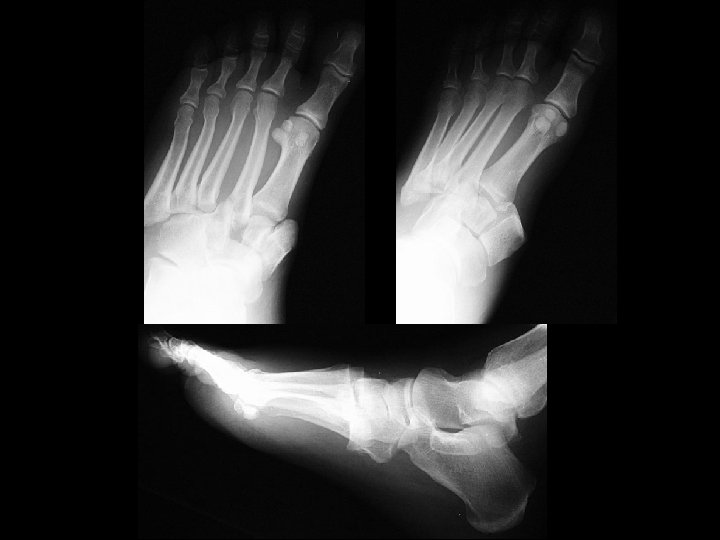

Osseous Calcaneonavicular coalition • Findings: – pes planus in a skeletally immature patient – enlongated anterior process of calcaneous = “anteater sign” – oblique view is diagnostic • ddx: – NONE! – This is an Aunt Minnie!

Fibrous Calcaneonavicular coalition • Findings: – pes planus in a skeletally immature patient – enlongated anterior process of calcaneous = “anteater sign” – oblique view is diagnostic • ddx: – NONE! – This is an Aunt Minnie!